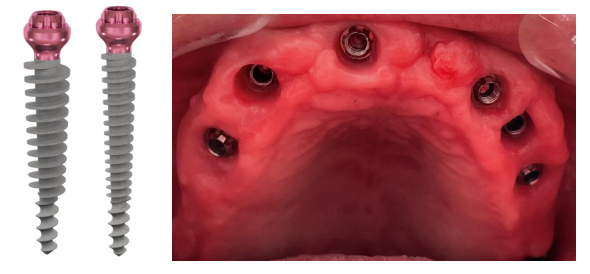

In the maxilla Compressive Implants P 3.5/20 mm (ROOTT) were placed in the extraction sockets and at position 18 and 28 for high primary stability. The high primary stability is achieved due to the specific characteristics of these implants (Fig 2). The long thin part guides the implant during insertion while the larger part with compressive threads compresses the bone which results in bone corticalization.

The implants were inserted to bone level so that the head can be at tissue level. The same procedure was done in the anterior part of mandible.

On the first appointment all teeth in the maxilla were extracted, and implants were placed, under local anesthesia. Pterygoid Implants C 3.5/20 mm were placed in position 18 and 28 to get a high primary stability, same implants were used at the extraction’s sockets and in the rest of the maxilla figure 7